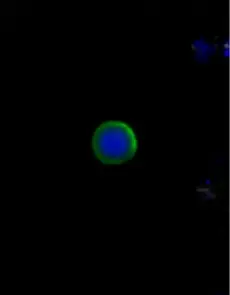

Example images from patient blood samples

Cluster of EMT CTCs - breast